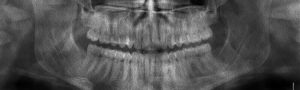

Péče o ústní zdraví nekončí jen jednoduchou prohlídkou v ordinaci zubního lékaře. Primárním krokem je komplexní každodenní dentální hygiena, která je klíčová pro prevenci vzniku onemocnění